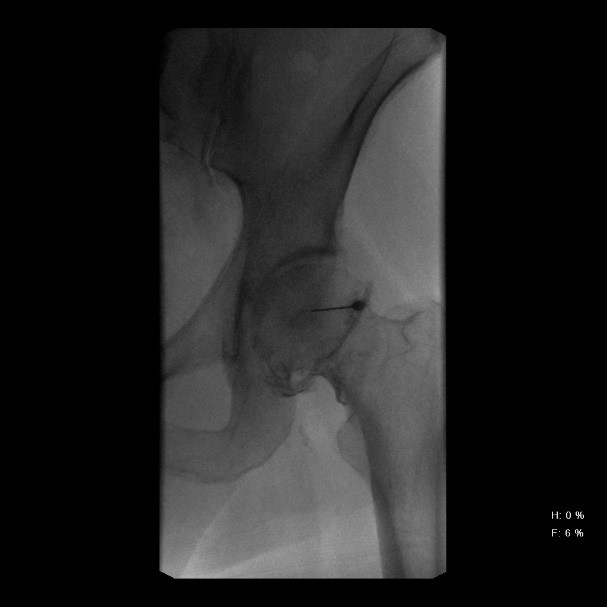

Για να πετύχει απόλυτα η έγχυση των Βλαστοκυττάρων, πρέπει η άρθρωση να προετοιμασθεί για διάστημα 6 εβδομάδων με έγχυση (μέσω ακτινοσκοπικής TV) Βιολογικών παραγόντων του αίματος, το αποκαλούμενο PRF υπό μορφή ζέλης (από το αίμα του ασθενούς).

Σχετικά με τη θεραπεία της Οστεοαρθρίτιδας του Ισχίου και των Γονάτων, το PRF χρησιμοποιείται για την αναγέννηση του χόνδρου και την ανακούφιση από τον πόνο που προκαλείται από την εκφυλιστική διαδικασία του χόνδρου στις αρθρώσεις.

Το PRF εγχύεται στην περιοχή της άρθρωσης που πάσχει, όπου οι αυξητικοί παράγοντες που περιέχονται στο πλάσμα ενισχύουν την ανάπλαση των ιστών και βοηθούν στη μείωση της φλεγμονής και του πόνου.